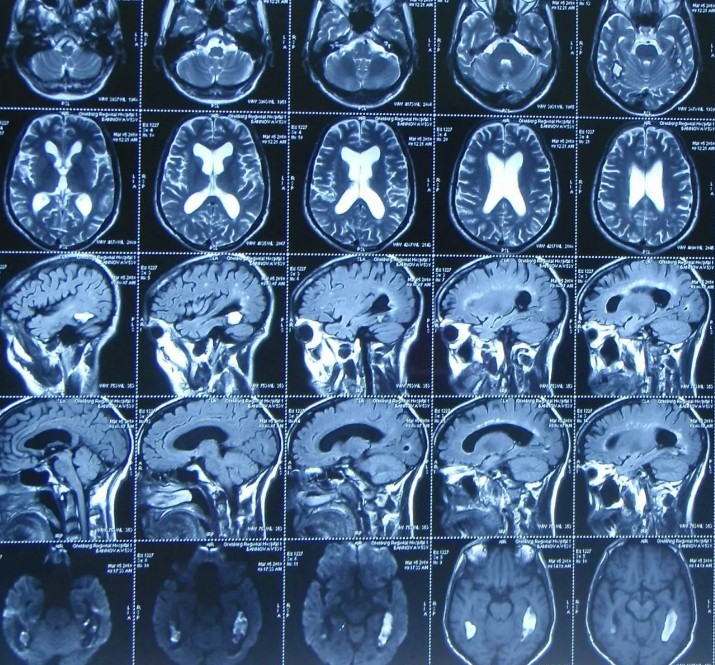

Шум в голове мрт головы

Шум в голове мрт головы 132 фотографий